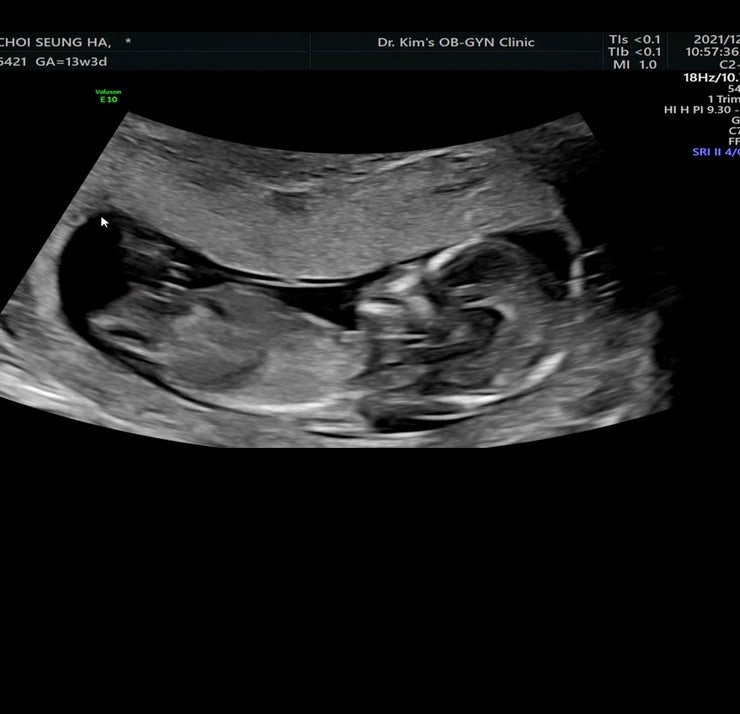

찰떡이 13주3일 /정밀초음파

13주3일 정밀초음파 크리스마스 이브^^ 찰떡이 초기정밀 초음파를 보고왔다 오늘은 신랑도 함께했다~ 일주...